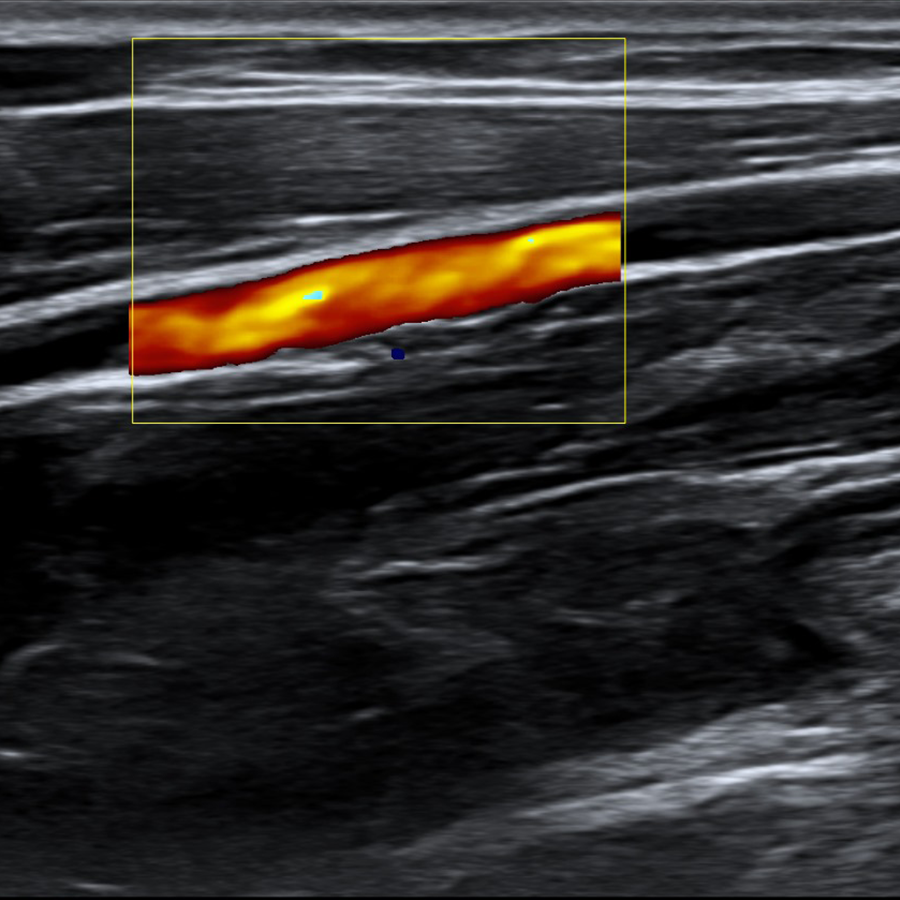

Radiología

- IMT Automática

- VFlow+

- IMT en Tiempo Real